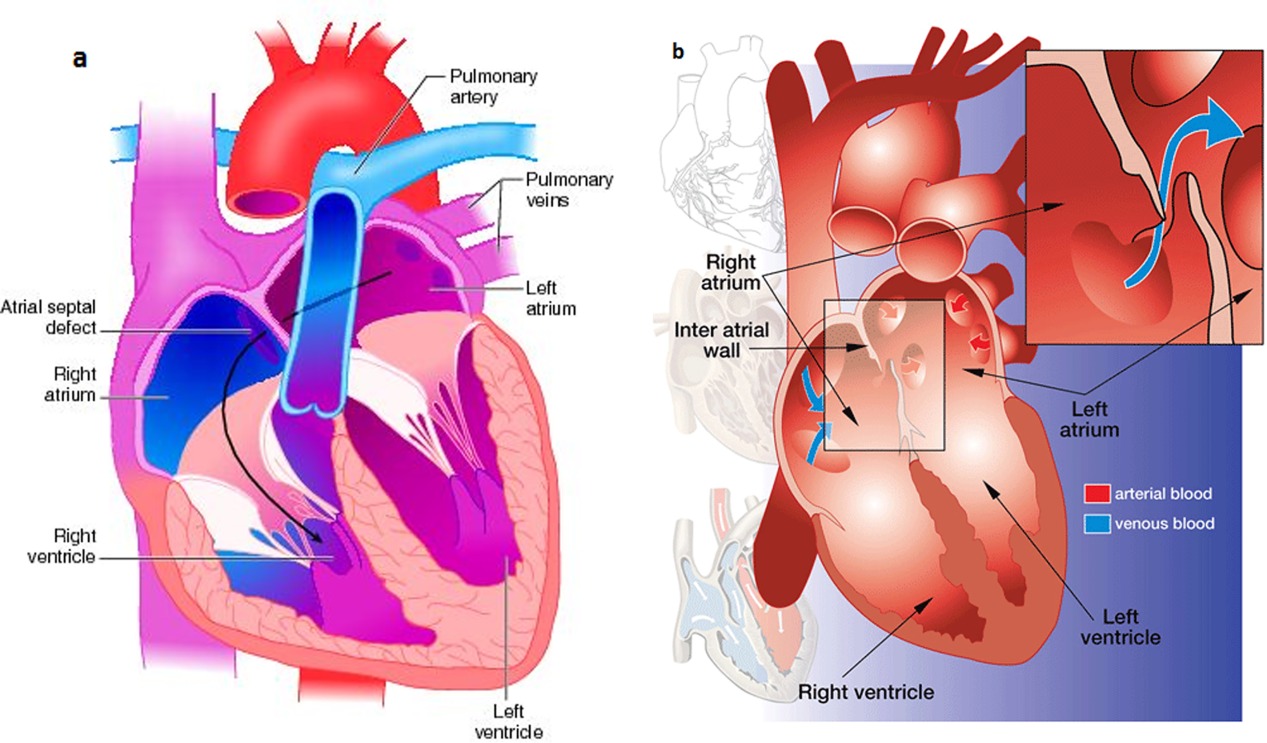

Value added benefits of the ASD Surgical Closure Open Surgery:

Ø Doctor consultation charges

Ø Lab tests and diagnostic charges

Ø Room charges inside hospital during the procedure

Ø Surgeon Fee

Ø Nursing charges

Ø Hospital surgery suite charges

Ø Anesthesia charges

Ø Routine medicines and routine consumables (bandages, dressings etc.)

Ø Food and Beverages inside hospital stay for patient and one attendant.

Extra benefits:

ü Interpreter

ü Visa assistance

Ø Site tourism of the city

Ø Follow up with the doctor

Ø Airport pick up and drop

Ø Free online consultation with the doctor

Ø Priority appointments with the doctor

Ø Room upgrade from sharing to private

Value added benefits of the ASD Closure:

Ø Doctor consultation charges

Ø Lab tests and diagnostic charges

Ø Room charges inside hospital during the procedure

Ø Surgeon Fee

Ø Nursing charges

Ø Hospital surgery suite charges

Ø Anesthesia charges

Ø Routine medicines and routine consumables (bandages, dressings etc.)

Ø Food and Beverages inside hospital stay for patient and one attendant.

Extra benefits:

ü Interpreter

ü Visa assistance

Ø Site tourism of the city

Ø Follow up with the doctor

Ø Airport pick up and drop

Ø Free online consultation with the doctor

Ø Priority appointments with the doctor

Ø Room upgrade from sharing to private